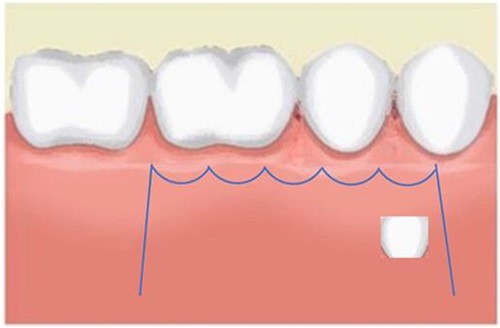

A Neumann full-thickness buccal flap was utilized to remove these during the course of orthodontic treatment. The shortcoming of the buccal surgical removal approach is that although it is better for visualization, it poses a high risk of trauma to the adjacent teeth or nerves [4, 5]. As the premolar was being removed on the right side, there was a fracture of the root apex (Fig. 2). On the left side, the premolar bud could be removed without any trauma to the adjacent tooth roots. After months of follow-up, there was normal bone formation, and no other symptoms were identified (Fig. 3).

Follow-up panoramic image 1-year after removal of the supernumerary premolars.